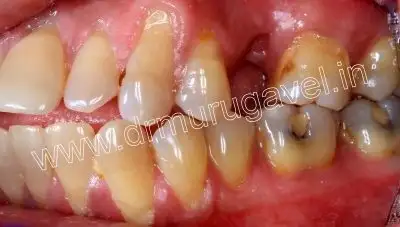

Before treatment

Front view

Upper view

Side view